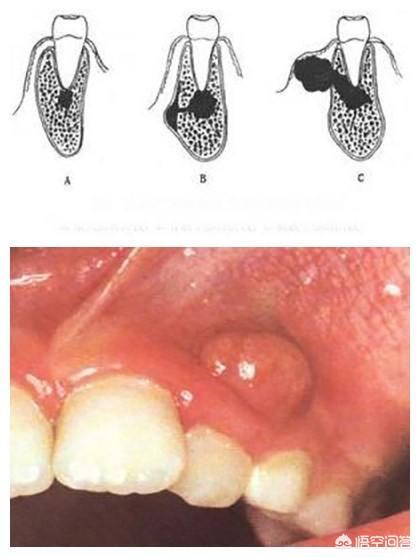

1.智歯周囲炎

歯が虫歯になったり外傷を受けたりすると、細菌が歯髄組織に侵入し、感染が歯根周囲組織に広がり、歯根周囲炎に発展すると、歯がゆるくなり、浮遊感や咀嚼時の痛みを伴うようになります。

1.智歯周囲炎の治療

根尖周囲炎の最良の治療法は根管治療です。医師は特殊な器具を使って根管内の感染を除去し、生体適合性のある材料で根管内を密閉することで、感染の再侵入を防ぎます。根尖周囲炎が治まった後、歯がゆるくなったり、浮いたような感じになったりすることはありません。

3.智歯周囲炎.罹患歯の智歯周囲に炎症がある場合、特に急性炎症では、罹患歯は浮遊感を示し、歯が緩む。

治療プログラムドレナージ+抗炎症剤で急性炎症症状を緩和し、急性炎症が治まった後、歯の状態に応じて、歯根膜病変を根管治療して患歯を残すか、抜歯するかを決める。

4. 顎の嚢胞性腫瘍などの病変。歯を包む顎骨に嚢胞や腫瘍などの病変があり、顎骨の骨質が著しく変化している場合、病変部位の歯は緩みます。

治療法:顎病変の外科的治療、病巣部の抜歯、歯根端手術。